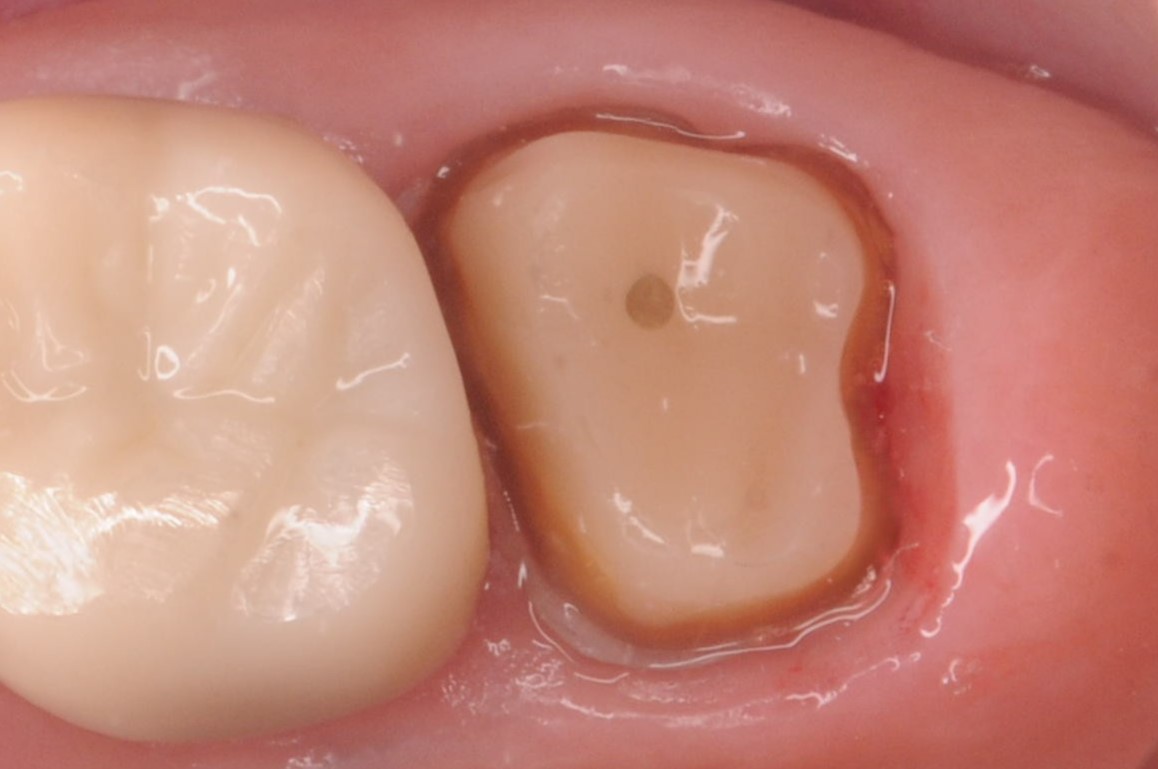

噛んだ時の違和感を訴えられ、以前のセラミックスクラウンを除去し根管治療開始。

ラバーダム下での2回の根管治療を経て、根管充填と支台築造を行った状態から、精密なクラウン用の形成と印象を行い、セラミックスクラウンの装着。